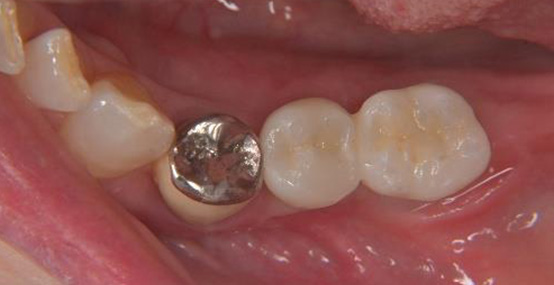

上部構造装着後の写真です(スクリュー固定の被せものを装着しています)

左:最終的な被せものの装着時の状態

中:インプラントのホール(穴)を樹脂で封鎖した後

右:装着後の状態のレントゲン写真です

上:最終的な被せものの装着時の状態

下:装着後の状態のレントゲン写真です